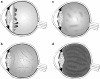

The entity described by Gunnar Stickler, which included hereditary arthro-ophthalmopathy associated with retinal detachment, has recently been recognised to consist of a number of subgroups, which might now more correctly be referred to as the Stickler syndromes. They are the most common clinical manifestation of the type II/XI collagenopathies and are the most common cause of inherited rhegmatogenous retinal detachment. This review article is intended to provide the ophthalmologist with an update on current research, subgroups, and their diagnosis together with a brief overview of allied conditions to be considered in the clinical differential diagnosis. We highlight the recently identified subgroups with a high risk of retinal detachment but with minimal or absent systemic involvement--a particularly important group for the ophthalmologist to identify.